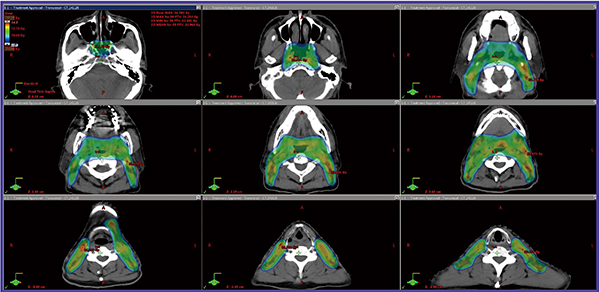

●症例1:ワルダイエル輪原発のびまん性大細胞型B細胞リンパ腫 stageⅡ

薬物療法R8CHOP3療法にてmetabolic CRとなり,地固め治療としてRapidArcを用いた30 Gy/15回のISRTを行った。急性毒性として,咽頭粘膜の発赤と軽微な嚥下時不快感,味覚低下,一時的な口渇を認めたのみであった。線量分布図を図1に示す。

図1 症例1:ワルダイエル輪原発のびまん性大細胞型B細胞リンパ腫 stageⅡに対するRapidArcを用いたISRTの例